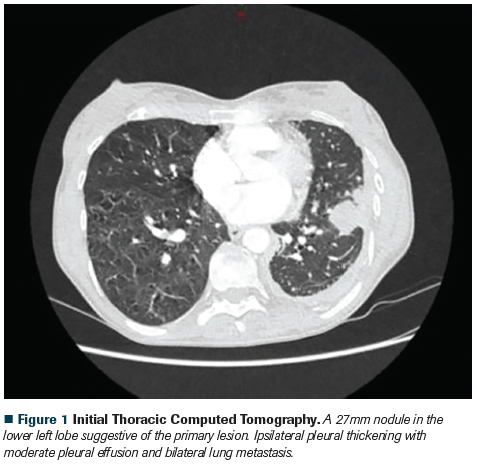

Figure 1 Initial Thoracic Computed Tomography

A chest computed tomography (CT) scan was performed which showed a 30-mm lung nodule in the lower left lobe and mediastinal and ipsilateral pleural thickening with moderate pleural effusion and several bilateral lung metastases. The patient underwent a CT-guided lung biopsy. The pathology evaluation revealed a well-differentiated lepidic lung adenocarcinoma (positive for cytokeratin 7, thyroid transcription factor 1 , and napsin A). Brain magnetic resonance imaging with contrast revealed the presence of 2 occipital metastatic lesions without surrounding edema. She denied headaches, nausea, vomiting, visual alterations or focalization symptoms.